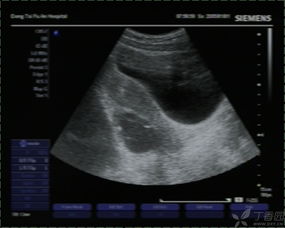

常規(guī)B超檢查是不需要空腹的,因為它不受消化道氣體的影響,常規(guī)B超檢查主要是通過B超的探測頭在腹部進行探測,從而檢查女性的子宮以及盆腔部位。并且懷孕的女性做B超,一般也是做常規(guī)B超檢查,而不是采取陰道B超檢查,因為能夠最大的保護胎兒。

做常規(guī)B超檢查需要注意的一個地方,就是最好在B超檢查時能夠補充大量的水分,讓膀胱充盈起來,這樣才能讓結果更加的準確和清晰。早孕的女性需要補充水分,孕13周以后的女性在做常規(guī)B超檢查的時候就不需要喝水,讓膀胱充盈了。

肝膽胰等部位的B超檢查需要空腹,因為肝膽胰位于盆腔腹部的深處,因此也就特別容易受到消化道氣體的影響,如果不空腹去進行檢查就非常容易使結果產(chǎn)生偏差,從而達不到檢查的目的。

做B超檢查的時候是否空腹,主要是看具體是針對哪一部位的B超檢查,要具體情況具體分析。如果不知道自己做的B超檢查是否要空腹,需要提前就咨詢醫(yī)生,以免耽誤檢查的時間。